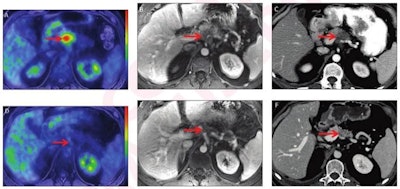

52-year-old man with locally advanced pancreatic adenocarcinoma and major pathologic response. Pretreatment (A-C) and post-treatment (D-F) images after eight cycles of systemic Folfirinox and consolidative chemoradiation. Baseline CA 19-9 was 145 U/ml. Pretreatment whole-body axial fused PET/MRI showed FDG-avid lesion in body of pancreas (arrow, A) with SUVmax 7.1 and SUVgluc 8.0. Lesion was hypoenhancing on axial contrast-enhanced T1-weighted MR image (arrow, B) from focused abdominal PET/MRI and on CT (arrow, C). Pretreatment CT tumor volume was 10.3 cm3. Post-treatment whole-body axial fused PET/MRI showed complete metabolic response (arrow D) with SUVmax 1.9 and SUVgluc 1.9. Lesion was indistinct on axial contrast-enhanced T1-weighted MRI (arrow, E) and CT (arrow, F), and there was upstream pancreatic parenchymal atrophy. Post-treatment CT tumor volume was 0.46 cm3. There was normalization of CA 19-9. Relative change in SUVmax was -73%, and relative change in SUVgluc was -76%. Based on change in tumor size, response was categorized as partial response per RECIST. Relative change in tumor volume was -96%. Pathology showed major pathologic response (College of American Pathologists score 1). Images and caption courtesy of the American Roentgen Ray Society and the American Journal of Roentgenology.Panda and colleagues found that pre- and post-treatment changes in tumor metrics on PET/MRI and CT were associated with pathologic response.